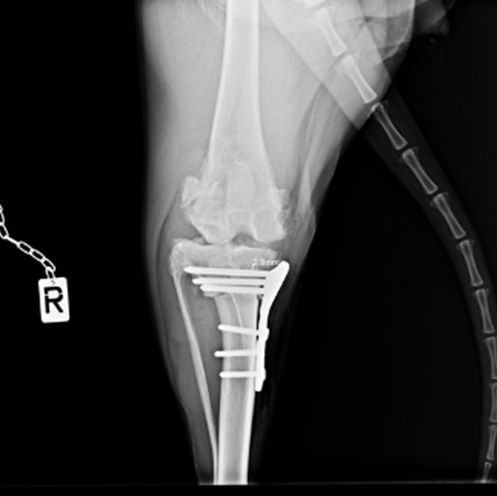

• Orthopédie

Une salle de chirurgie est spécifiquement et uniquement dédiée à l'orthopédie.

L'orthopédie se consacre à l'étude des maladies de l'appareil locomoteur : os, articulations, muscles, tendons, ligaments... Chez les chiens et les chats, ces affections sont fréquentes, entrainant douleur, boiterie, difficultés pour marcher, pour sauter...

Le Dr Lionel SIMON s'intéresse particulièrement à ce domaine et sera ravi de vous recevoir sur rendez-vous.